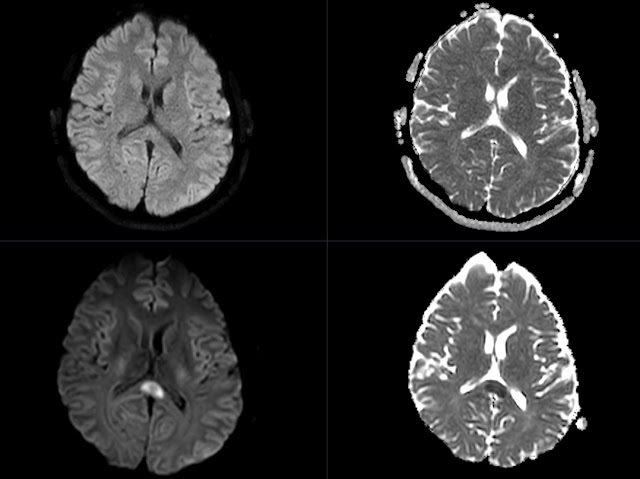

45 years old patient on antiepileptic (lamotrigine) and antidepressant medication. Presents with unspecific neurological symptoms. MRI without contrast shows diffusely demarcated oval lesion with edema in splenium of corpus callosum.

Diffusion weighted imaging shows restricted diffusion with high signal on DWI and low on ADC corresponding with cytotoxic edema. However location is not specific for infarction. Given the history of treatment together with appearance of the lesion the Cytotoxic Lesions Of the Corpus Callosum (CLOCCs) was presumed to be the most likely diagnosis. CLOCCs do no enhance. Medication was stopped and follow up scan was scheduled.

No diffusion restriction was noted on the control scan - compared with initial MRI.